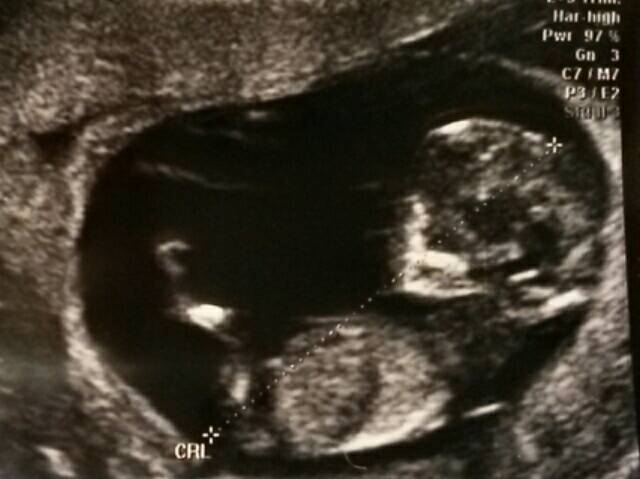

Mietin pitkään, laitanko koko kuvia tänne, kun keskustelu on ollut kovin alamaissa viime päivinä. Laitan nyt kuitenkin. Jos joku pahoittaa mielensä tai loukkaantuu, olen pahoillani.

Kävimme tänään np-ultrassa. Kaksi kaverusta siellä edelleen jumppasi. Niskaturvotusta oli kummallakin alle 1mm ja muutenkin sikiöillä oli kaikki palikat paikoillaan. Kahden kätilön voimin selvittivät sitten, minkä tyyppinen raskaus on kyseessä ja molemmille löytyivät omat istukat ja kaikki muukin oli omaa. Eli paras mahdollinen tilanne tässä vaiheessa. Kokoa kaveruksilla oli sen verran, että vastaavat viikkoja 12+1 ja 11+6. Ihan viikkoja vastaavat ovat siis.

Saatiin mukaan ihan hirveästi kuvia ja ultrassakin meni aikaa toista tuntia. Olisi ruutua kyllä pidempäänkin vielä katsellut. Sen verran veikeän näköistä oli kaverien meno. Selvästi olivat jakaneet vuorot, että kun toinen lepää, toinen riehuu ja sitten vaihdetaan. Onneksi asennot olivat hyvät, että kätilö sai kaikki tarpeelliset mitat otettua.

En olisi kyllä viime kevään keskenmenon jälkeen ikinä uskonut, että tähän pisteeseen vielä päästään. Eikä se ihan todelta vieläkään tunnu. Toivon sydämeni pohjasta, että ihan jokainen saa saman kokea ennemmin tai myöhemmin! ♡